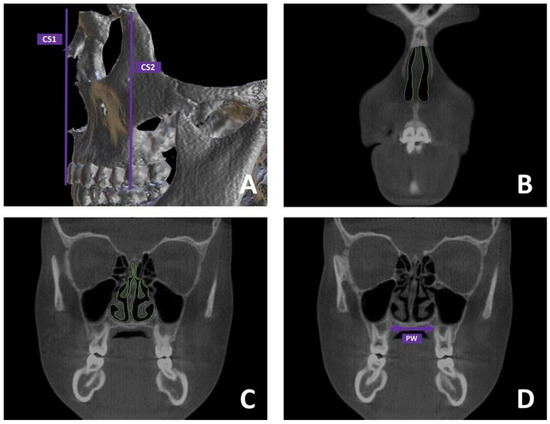

2.2.3. Skeletal Measurements

| PW (mm) | ||||||||||||

| T0 | 24.16 | (22.64–29.13) | <0.001 | 22.64 | (20.89–25.19) | <0.001 | 23.68 | (21.37–25.98) | <0.05 | 0.231 | ||

| T1 | 26.87 | (23.95–31.59) | 24.99 | (22.81–27.48) | 26.04 | (24.53–28.14) | 0.379 | |||||

| T1-T2 | 2.71 | (0.77–3.34) | - | 2.35 | (0.97–2.91) | - | 2.36 | (0.61–4.46) | - | 0.406 | ||

| Change (%) | 11.22 | 10.38 | 9.97 | |||||||||

| CS1 (mm2) | ||||||||||||

| T0 | 166.09 | (140.07–191.28) | <0.001 | 156.40 | (126.28–175.10) | <0.001 | 198.11 | (169.18–213.41) | <0.001 | 0.092 | ||

| T1 | 199.32 | (176.64–218.49) | 192.76 | (178.26–204.32) | 228.56 | (189.96–248.93) | 0.121 | |||||

| T1-T2 | 33.23 | (11.15–54.03) | - | 36.36 | (15.01–50.50) | - | 30.45 | (18.02–45.11) | - | 0.532 | ||

| Change (%) | 20.01 | 23.25 | 15.37 | |||||||||

| CS2 (mm2) | ||||||||||||

| T0 | 235.4 | (222.65–271.08) | <0.001 | 198.67 | (190.01–235.91) | <0.05 | 217.25 | (195.25–228.99) | <0.05 | 0.256 | ||

| T1 | 270.89 | (236.83–312.50) | 228.56 | (209.10–251.27) | 236.17 | (202.53–261.31) | 0.441 | |||||

| T1-T2 | 35.49 | (9.10–46.66) | - | 29.89 | (6.40–44.13) | - | 18.92 | (0.75–32.32) | - | 0.358 | ||

| Change (%) | 15.08 | 15.05 | 8.71 | |||||||||